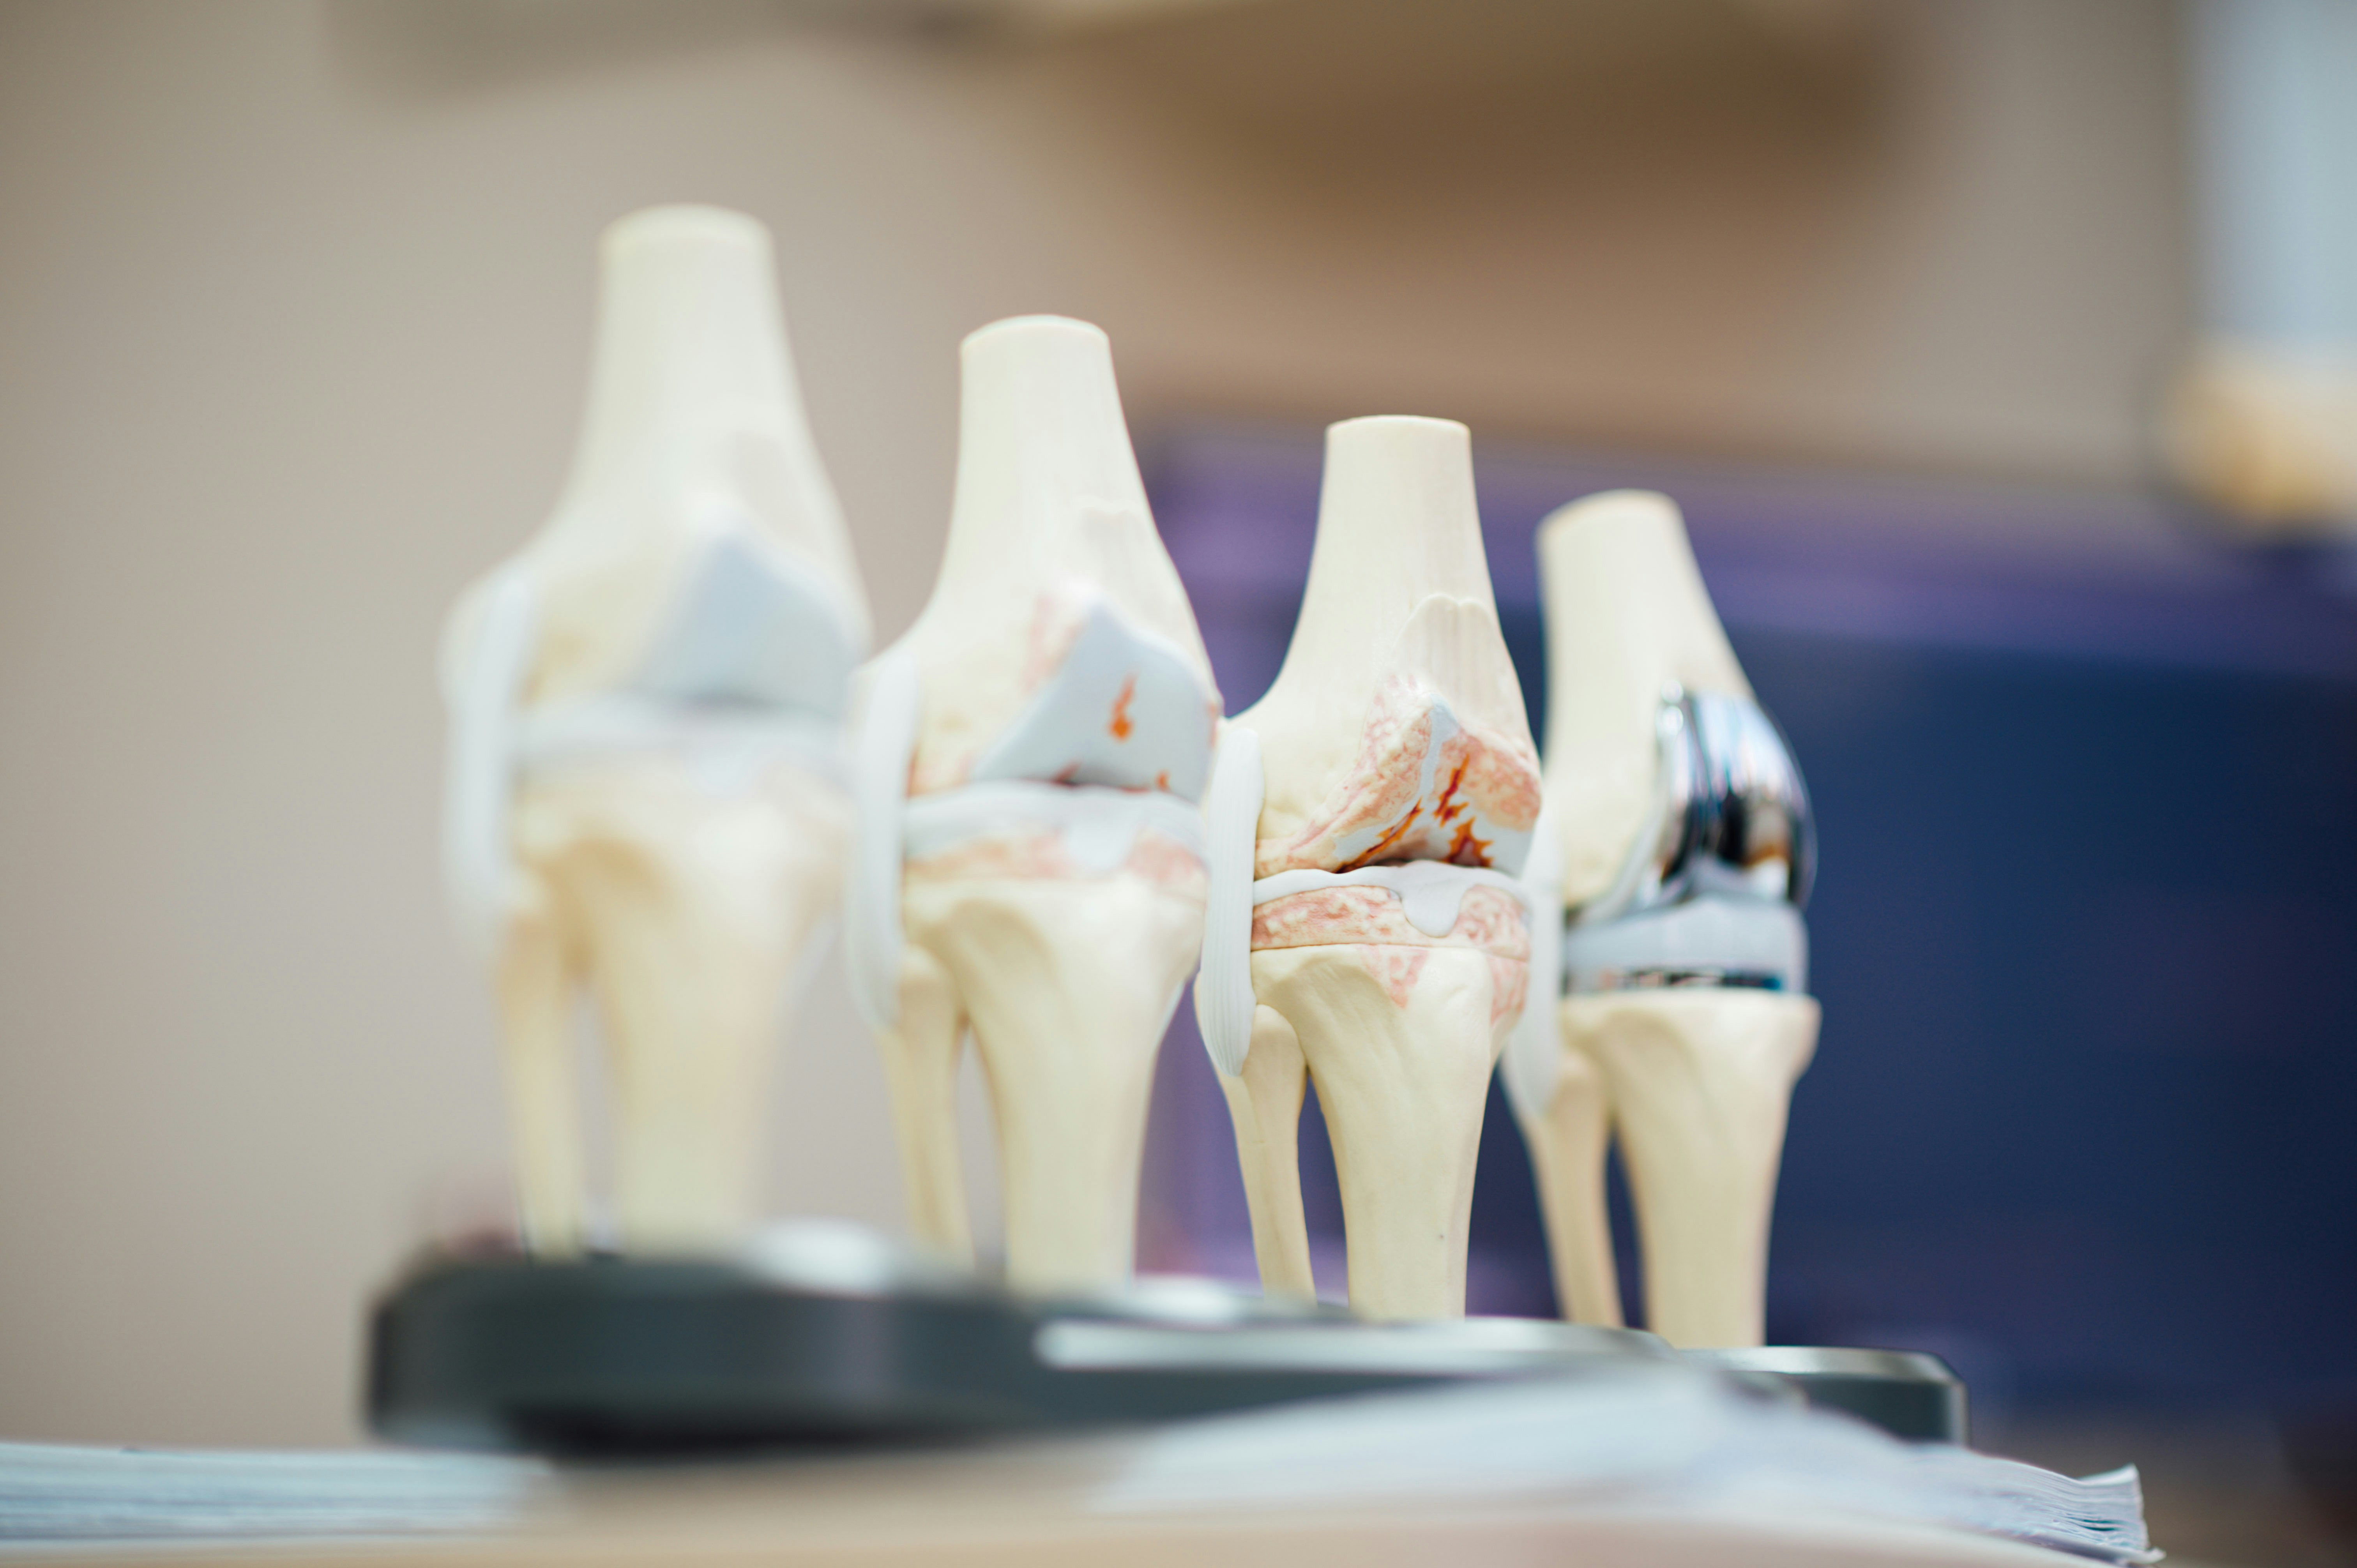

가장 흔한 원인은 관절을 보호하고 있는 **연골의 마모**입니다. 오랜 시간 관절을 사용하면서 연골이 얇아지고 뼈와 뼈가 직접 부딪히게 되는데, 이때 극심한 통증과 부종이 발생합니다. 주로 체중 부하가 큰 무릎이나 고관절, 손가락 끝마디에 자주 나타나며 저녁 시간대에 통증이 심해지는 특징이 있습니다.

관절 질환별 증상 비교표

| 질환 종류 | 주요 통증 부위 | 통증 발생 시간 |

|---|---|---|

| 퇴행성 관절염 | 무릎, 엉덩이, 손가락 끝 | 활동 후 저녁 시간 |

| 류마티스 관절염 | 손목, 손가락 중간 마디 | 아침 기상 직후 |

| 통풍 | 엄지발가락, 발목 | 갑작스러운 급성 통증 |